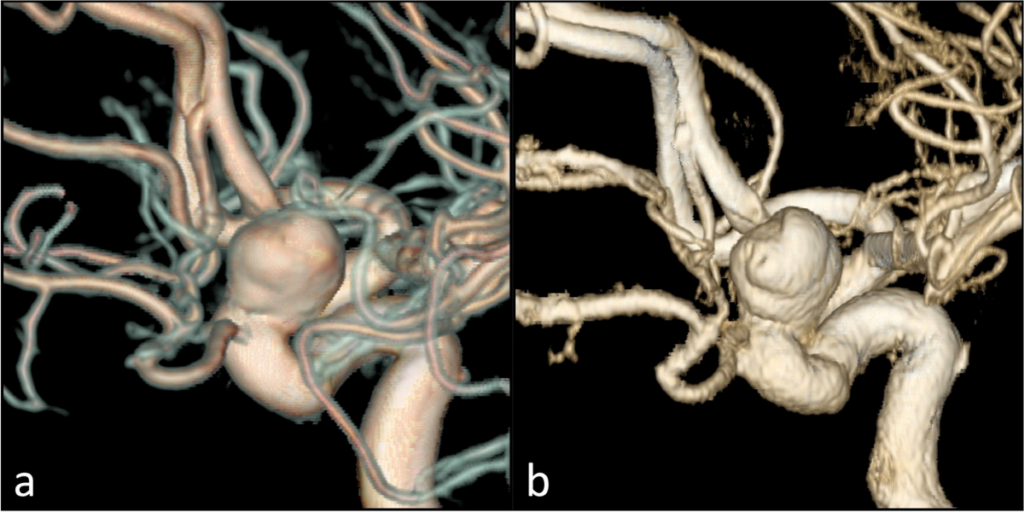

MRI 顯示大的腦血管動脈瘤 Big Cerebral Aneurysm

腦血管動脈瘤 Cerebral Aneurysm

腦動靜脈畸形血管瘤 Cerebral Arteiovenous Mlaformation AVM